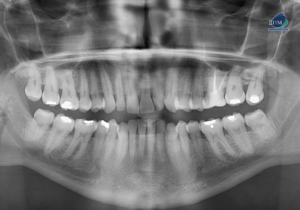

Paciente femenina de 46 años, es referido al Instituto de Diagnóstico Maxilofacial – IDM (Sede Surco) para evaluación general. Radiografia Panorámica En la radiografía panorámica